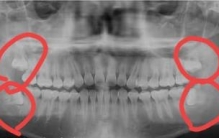

• 怎么知道自己会不会长智齿(长智齿脸都肿了)

怎么知道自己会不会长智齿(长智齿脸都肿了)

平时注意自己口腔的情况,长智齿,萌发处的的牙龈可能红肿,还有可能会伴有疼痛。发现这些情况可以找医生看看,如果是长智齿医生应该会发现的。 有龋齿或者其它口腔牙周问题去看牙医,也可以自己注意一下检查时拍的x ...